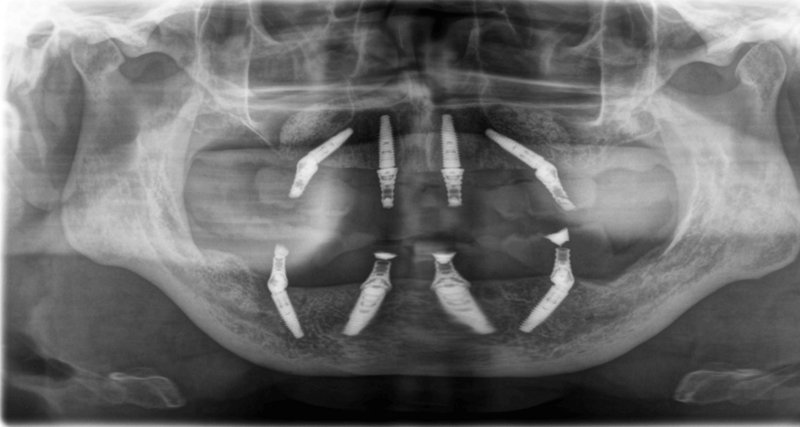

Durch den starken Neigungswinkel der Implantate wird sowohl im Ober- als auch im Unterkiefer eine Versorgung von 6 bis 6 möglich. Dies reduziert unter anderem die Länge des Anhängerabschnitts und ermöglicht die Sofortbelastung der Brückenkonstruktion. Trotz geringen Knochenangebotes sind vier Implantate zur Verankerung ausreichend.